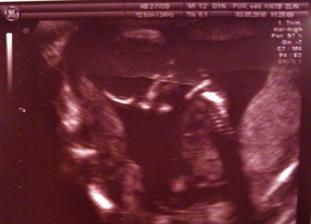

3.5. - screening ve Zlíně. Všechno v pořádku a zjistili jsme,že jsme o 5 dní starší, tedy 13+6tt. Prcek trochu zlobil a vzhledem k tt jsme UTZ absolvovali třikrát, protože nešel moc změřit. Nakonec se ale podařilo. Dostali jsme první fotku.:o) Manžel byl se mnou a byl na vývrat, když nás pořád posílali chodit, myslel, že za 15 minut budem hotový. Chlap🙂))

24.6. - 21+2tt poradna - vše ok, ale trošku jsem měla šok - 6kg navíc. Po kontrole jsem jela s kámoškou do Zlína na velký UTZ - čekáme zdravou holčičku a jsme moc šťastní.

31.8.- na mé narozeniny jsem se rozhodla jít na již zmiňovaný UTZ-neobjednává se. Všechno je v pořádku. Odhad váhy 1700g, placenta na přední stěně, Julinka je zadečkem dolů a tak máme dělat kočičí hřbet. Byl vidět pěkně obličej a jak vyplazuje jazyk.

20.10. - kontrola 38+1tt. Křivka krásná, pak běžná prohlídka a nakonec UTZ. Mimi je koncem pánevním - pravděpodobně půjdem na císařský řez. Byla jsem hned poslána i na předoperační vyšetření - tam mi vzali krev. Za dva dny pokračování. Stáří malé dle utz 37+4tt což sedí s 3.TP dle utz ve 12tt. Chtěla jsem rodit přirozeně, tak to byl trošku šok.☹